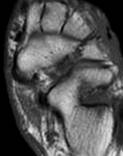

Как было указано во второй главе -,2 %) пациентам дообследование в ДКЦ№1 выполнялось с уже установленным ранее переломом и по окончании лечения, т. е. после консолидации перелома, но с выраженными жалобами на боли в области ГС.

|

| Рис. 5. Разрыв передней большеберцово-таранной связки; признаки консолидации перелома внутренней лодыжки (белая стрелка). |